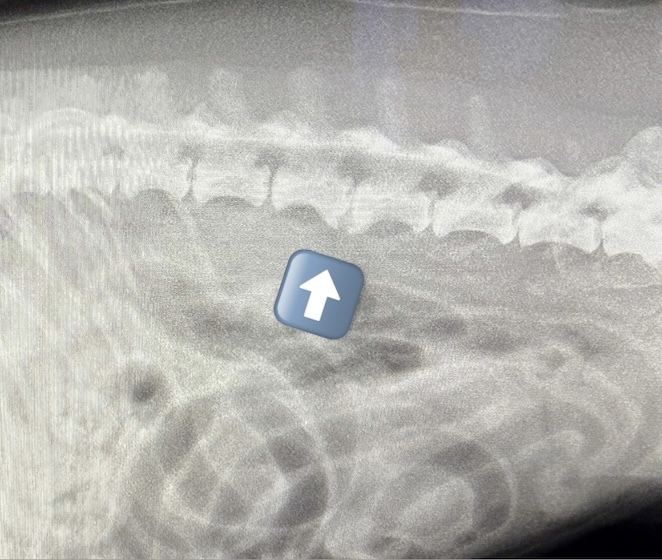

HPの外科の「その他の整形外科疾患」のページに、犬の足根関節の部分関節固定術を追加致しました。(コチラ)足根関節は脛骨、腓骨、踵骨、距骨、足根骨、中足骨と複数の骨で形成され、その関節構造は複雑であり複数の靭帯と腱で安定化されています。足根関節の脱臼や亜脱臼は、主に落下や激しい運動中の外傷によって生じます。症状として、患部は熱感を持って腫れ、動物は痛みにより後肢を挙上したり、負重を避けるように行動します患部g腫れ、動物は痛みにより歩行時や排泄時に体重がかからないように庇。治療法は、軽症の場合は副子や装具による保存療法を行いますが、重症の場合は靭帯修復や関節を固定する関節固定術を行う必要があります。歩行異常や足を庇うような仕草が認められる場合はお早めにご相談下さい。

獣医師 臼井